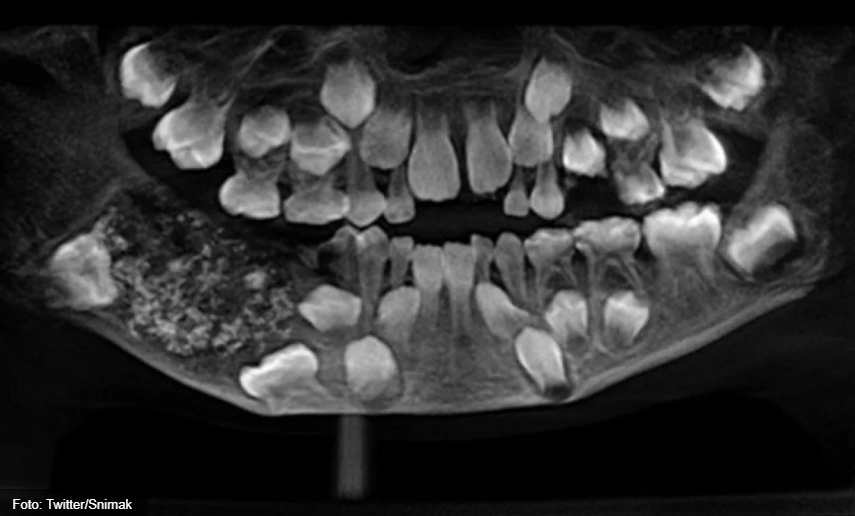

Snimak je pokazao zube različite veličine - od 0,1 do 15 milimetara, ugrađene u tumor u donjoj čeljusti.

"Izgledali su poput bisera. Čak je i najmanji zub imao krunu, korijen i caklinu", kazala je Ramani.